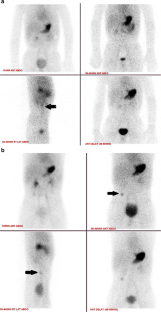

Fig. 1

Fig. 2

Fig. 3

Fig. 4